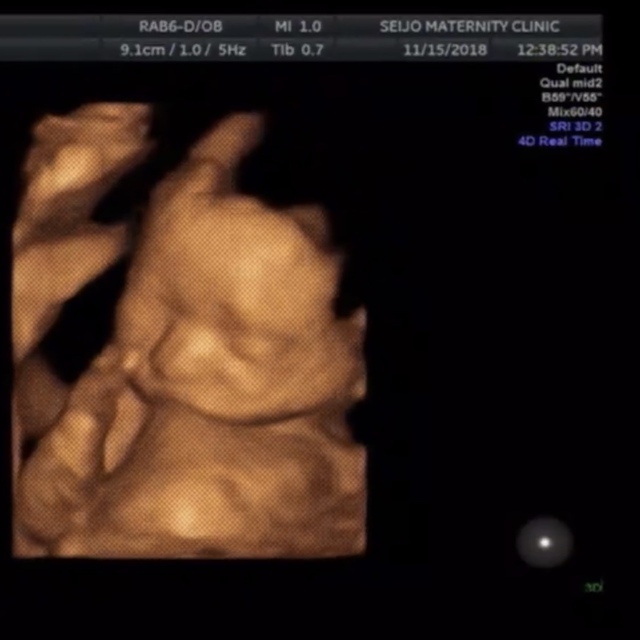

20週0日(20w0d・男の子)|saori 0104 さん

エコー写真撮影時のエピソード:

安定期に入った時に新居に引越しをし、病院を変えました。その時、初めての妊婦健診が胎児スクリーニングの時でした。胎児スクリーニングでは3Dエコーが見られるということで、初めての3Dエコーに私も主人も大興奮でした。助産師さんからは「この時期はみんな買おが一緒ですよ」と言われましたが、「このほっぺたが主人に似てる!」「鼻は私に似てるよね!」などと助産師さんお構いなしに盛り上がってしまったのはいい想い出です。

先程も記載した通り安定期に入った20週の頃にエコーを撮りましたが、私は妊娠悪阻で会社を1ヶ月半休職し、この頃は復帰して1ヶ月程たったときでした。今思うと1番体が動きやすく仕事もバリバリとやっていましたが、貧血が酷く電車の中で倒れることもしばしばありました。主人にはその度心配をかけさせてしまい、私の体調をすごく気にかけてくれました。健診には毎回ついてきてくれるので、一緒に赤ちゃんが産まれてきてくれることを楽しみにしてくれているんだなと感じます。